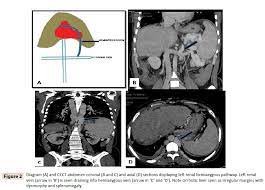

Some interventional radiologists prefer performing this. Le syndrome myéloprolifératif est la cause la plus fréquente de syndrome de Budd-Chiari 40-50.

Chiasmata -mə-tə or chiasmas also chiasms 1. Esophageal varices are extremely dilated sub-mucosal veins in the lower third of the esophagus. Located in metro Denver northern Colorado and western Nebraska serving all of the Front Range our team consists of board-certified and fellowship-trained interventional radiologists. This results in hepatic congestion similar to Budd-Chiari syndrome and post-sinusoidal portal hypertension. The patients condition should be monitored throughout the procedure. They are most often a consequence of portal hypertension commonly due to cirrhosis. Toxic injury to liver sinusoids causes sloughing of endothelial cells that embolize to hepatic venules and cause eventual fibrosis of the venules. Coin in the Esophagus. There is no clear consensus regarding the number of occluded veins some authors claim that there should be at least one occluded hepatic vein 7 others state that there are no significant.

Carcinoma of the Colon. Budd-Chiari syndrome a blockage in one or more veins that carry blood from the liver back to the heart. And coumarin skin necrosis adrenal gland hemorrhage and infarction. Toxic injury to liver sinusoids causes sloughing of endothelial cells that embolize to hepatic venules and cause eventual fibrosis of the venules. Chiari malformation CM is a structural defect in the cerebellum characterized by a downward displacement of one or both cerebellar tonsils through the foramen magnum the opening at the base of the skull. Embolism and thrombosis of. La présence dune ou plusieurs affections prothrombotiques est fréquente La prise en charge repose sur un traitement anticoagulant précoce le traitement de l.